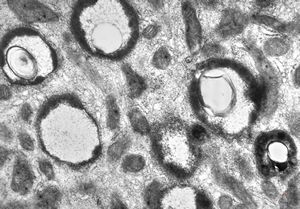

M,33y. | microsporidiosis (or cryptosporidiosis) - duodenum-posttransplantation immunodeficiency (HE and semithin section)

M,33y. | microsporidiosis (or cryptosporidiosis) - duodenum-posttransplantation immunodeficiency